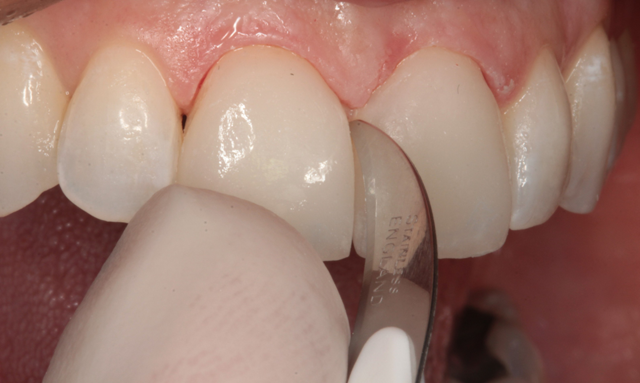

Figure 1 is a facial view of the first veneers in place. In the incisal view (Fig. 2), you can see that the veneers were used to close a central diastema. The reading from Vita Shade Light showed that the lateral incisors were 1M1 on the Vita 3D Shade Guide (Fig. 3).

Fig. 1 Fig. 2